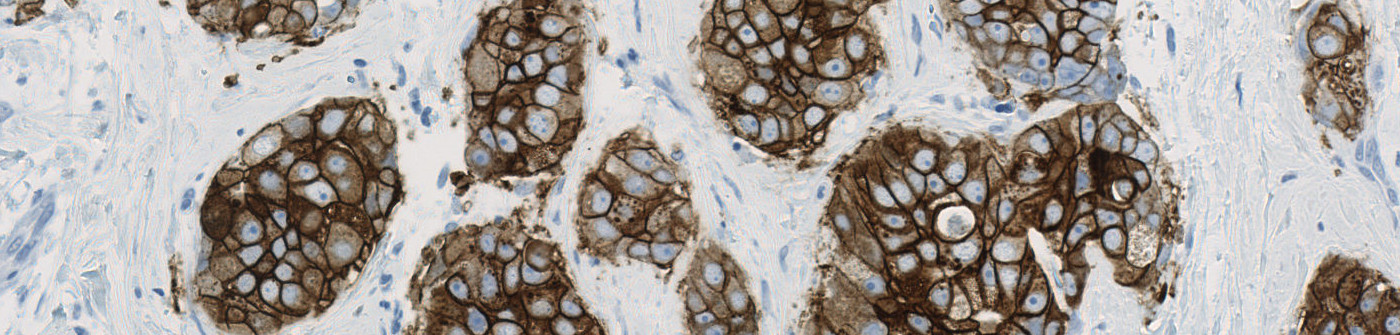

Field of view showing invasive tumor in an image of breast tissue stained by IHC for HER2 (brown).

The widely accepted ASCO/CAP recommendation for manual grading of breast cancer tissue sections stained by HER2 IHC includes four discrete scoring categories 0, 1+, 2+ and 3+, corresponding to negative, negative, equivocal, and positive for HER2 membrane staining, respectively. This scoring principle is based on determination of ratios of numbers of cancer cells with various degrees of membrane staining, and therefore requires quantifications to be made restrictively within tumor regions, and avoiding contributions from stromal and other non-cancer cells.

The present protocol is based on the Visiopharm HER2-CONNECT™ algorithm [2], which by automated image analysis determines the connectivity of the HER2-stained membrane in brightfield digital images of breast cancer tissue sections. The connectivity is a continuous measure of the size distribution of stained membrane fragments, and easily converts into the discrete scores 0, 1+, 2+, and 3+. The connectivity is unaffected by the presence of stromal and other non-cancer cells. The HER2-CONNECT™ algorithm therefore does not require manual outlining of the tumor region, and the operator only needs to define an overall region of interest.

The image analysis algorithm for this protocol involves several steps. First, a pre-processing step identifies the stained membrane pixels that contribute to linear structures in the image. Then, segmentation rules are employed identifying the membrane segments in the image. The segmentation is based on the intensity of brown in the pixels and the correct dimensions of linearity. By identifying tumor regions from stained membrane segments manual outlining of tumor regions become unnecessary. After identifying pixels that constitute to brown linear structures and make up part of a membrane segment, post-processing steps are employed. The post-processing steps are used to skeletonize the membrane, removing small membrane fragments and merging membrane fragments which are not perfectly connected. From the membrane fragments remaining after post-processing, the connectivity can be calculated.